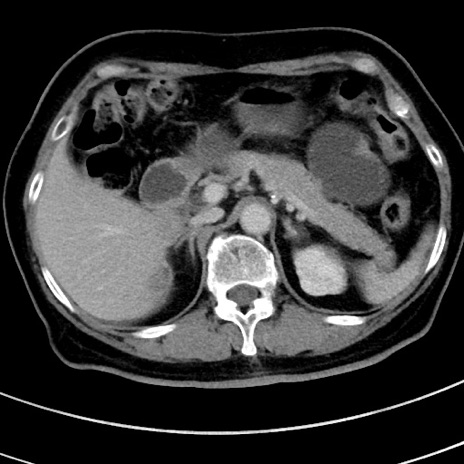

症例9(横断像)

【症例】 60歳代女性

【主訴】むかつき、みぞおちの痛み

【現病歴】3日前よりむかつきがあり、食事がとれない。

【既往歴】糖尿病

【身体所見】発熱なし、心窩部圧痛軽度あるも、腹膜刺激症状なし。

【データ】WBC 7400、CRP 1.92